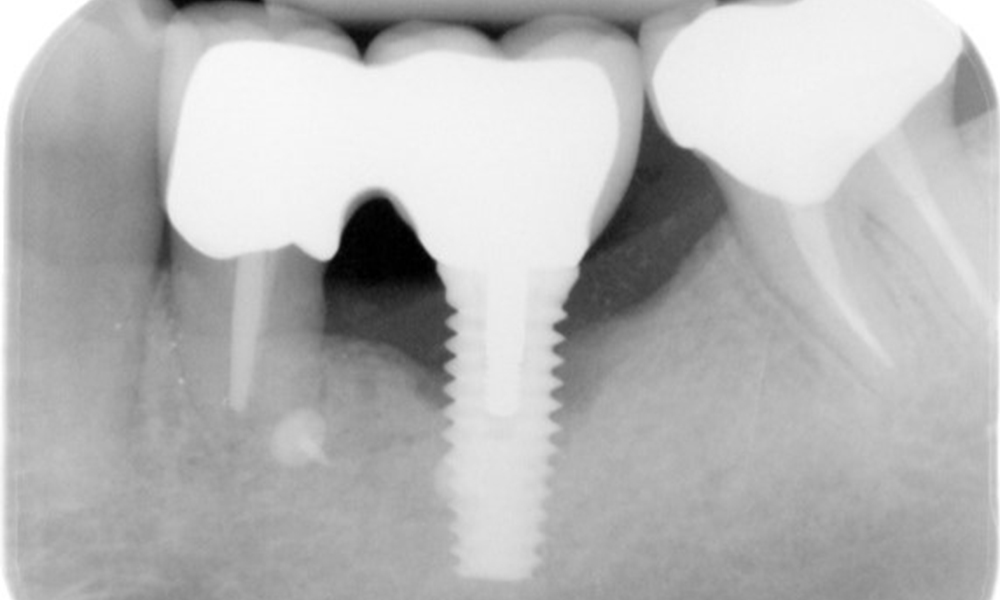

The X-ray images show the progression of bone loss in the area of the implant in region 36: dental film from 11.02.2021 (left) and dental film from 18.01.2024 (right).